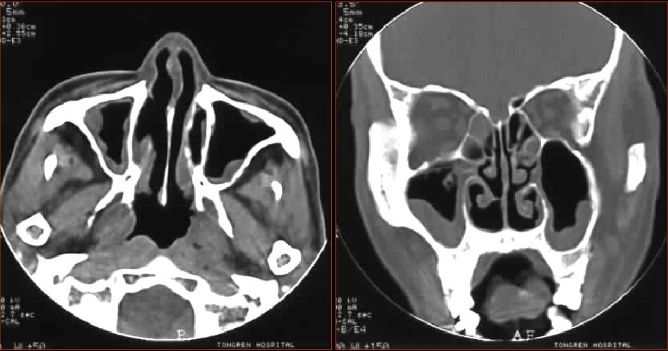

CT表现

● 冠状和水平位及HRCT技术

● 黏膜增厚

● 黏膜囊肿

● 骨质:吸收或硬化肥厚

● 并发症

慢性鼻窦炎—平片改变

慢性鼻窦炎—黏膜改变